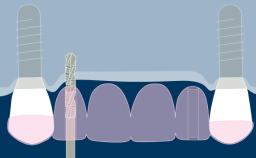

种植体支持式固定义齿旨在为缺失牙齿提供修复义齿,从而能承担相应的功能性需求,并且准确模拟缺失牙单位的美学效果。理想情况下,修复体应与周围牙齿难以分辨。为此,临床医生必须选择最佳的可用材料,来应对临床病情的种种挑战。本模块将讨论可用于制作种植体支持式固定义齿的牙科材料,以及为每个病例选择最合适的材料的基本原则。